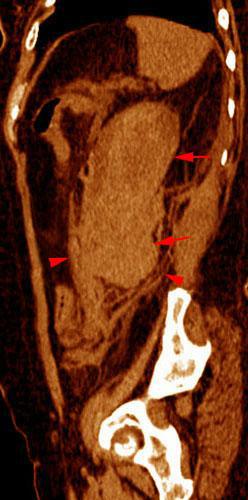

Rotura pielocalicial